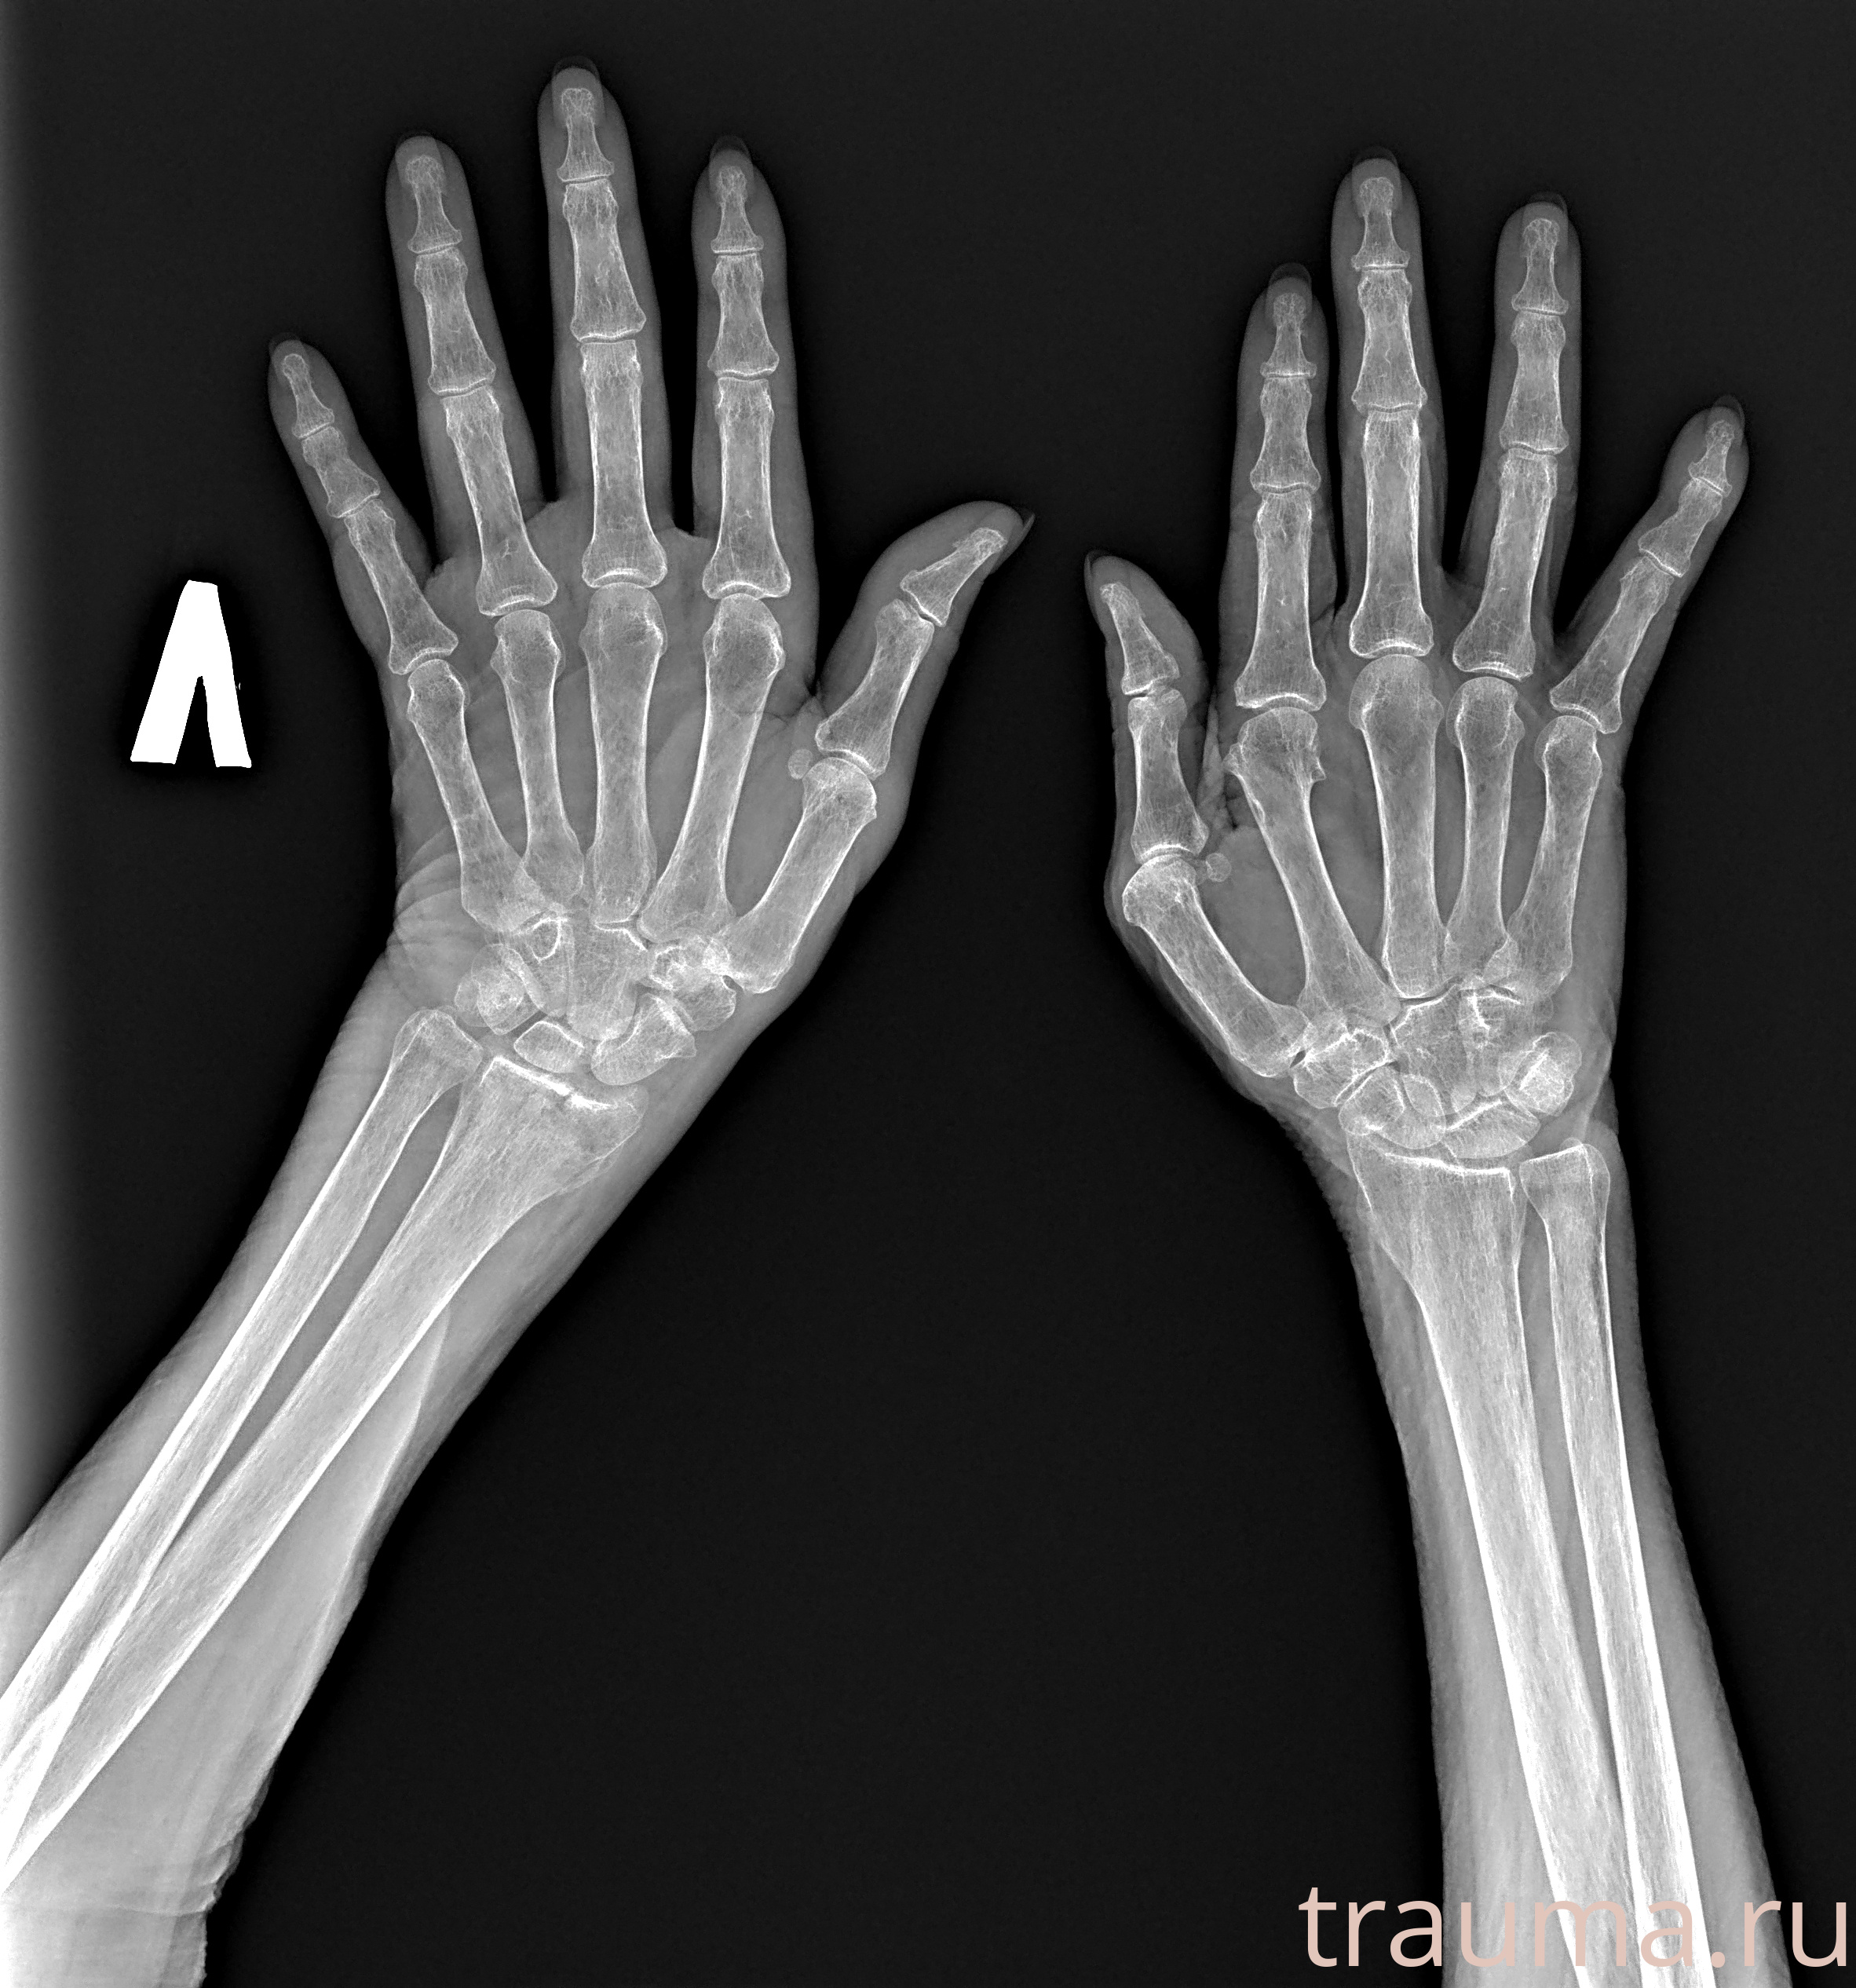

Рентген на дому: по вашему адресу приезжает врач-рентгенолог, травматолог-ортопед с мобильным рентгеновским аппаратом, проводит диагностику травмы или заболевания, делает необходимые рентгенограммы, дает рекомендации по дальнейшему лечению. Получить качественные снимки в домашних условиях возможно благодаря уникальной методике, разработанной МосРентген Центром для института  Склифосовского